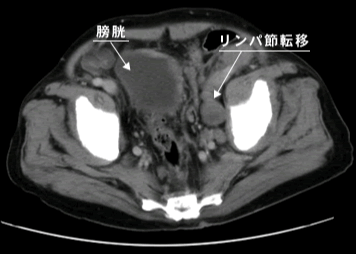

画像検査(CT、MRI)

CT

CT(コンピューター断層撮影法:computed(computerized) tomography)とMRI(磁気共鳴画像:magnetic resonance imaging)で、前立腺の周囲のリンパ節や臓器への転移、また、肺や肝臓などの遠隔臓器への転移を調べるために行います。

前立腺とその周囲のリンパ節や臓器、遠隔臓器をCT、MRIの画像に映し出すことによって、がんが前立腺内にとどまっているのか、周囲の臓器に浸潤しているのか、または遠隔臓器やリンパ節に転移しているのか、などを確認することができます。

骨盤部CT画像